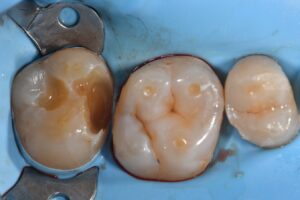

October 13, 2025 Direct Restoration #ClamplessDME #GarrisonCompositight #MajestyES2Universal Previous Post Next Post